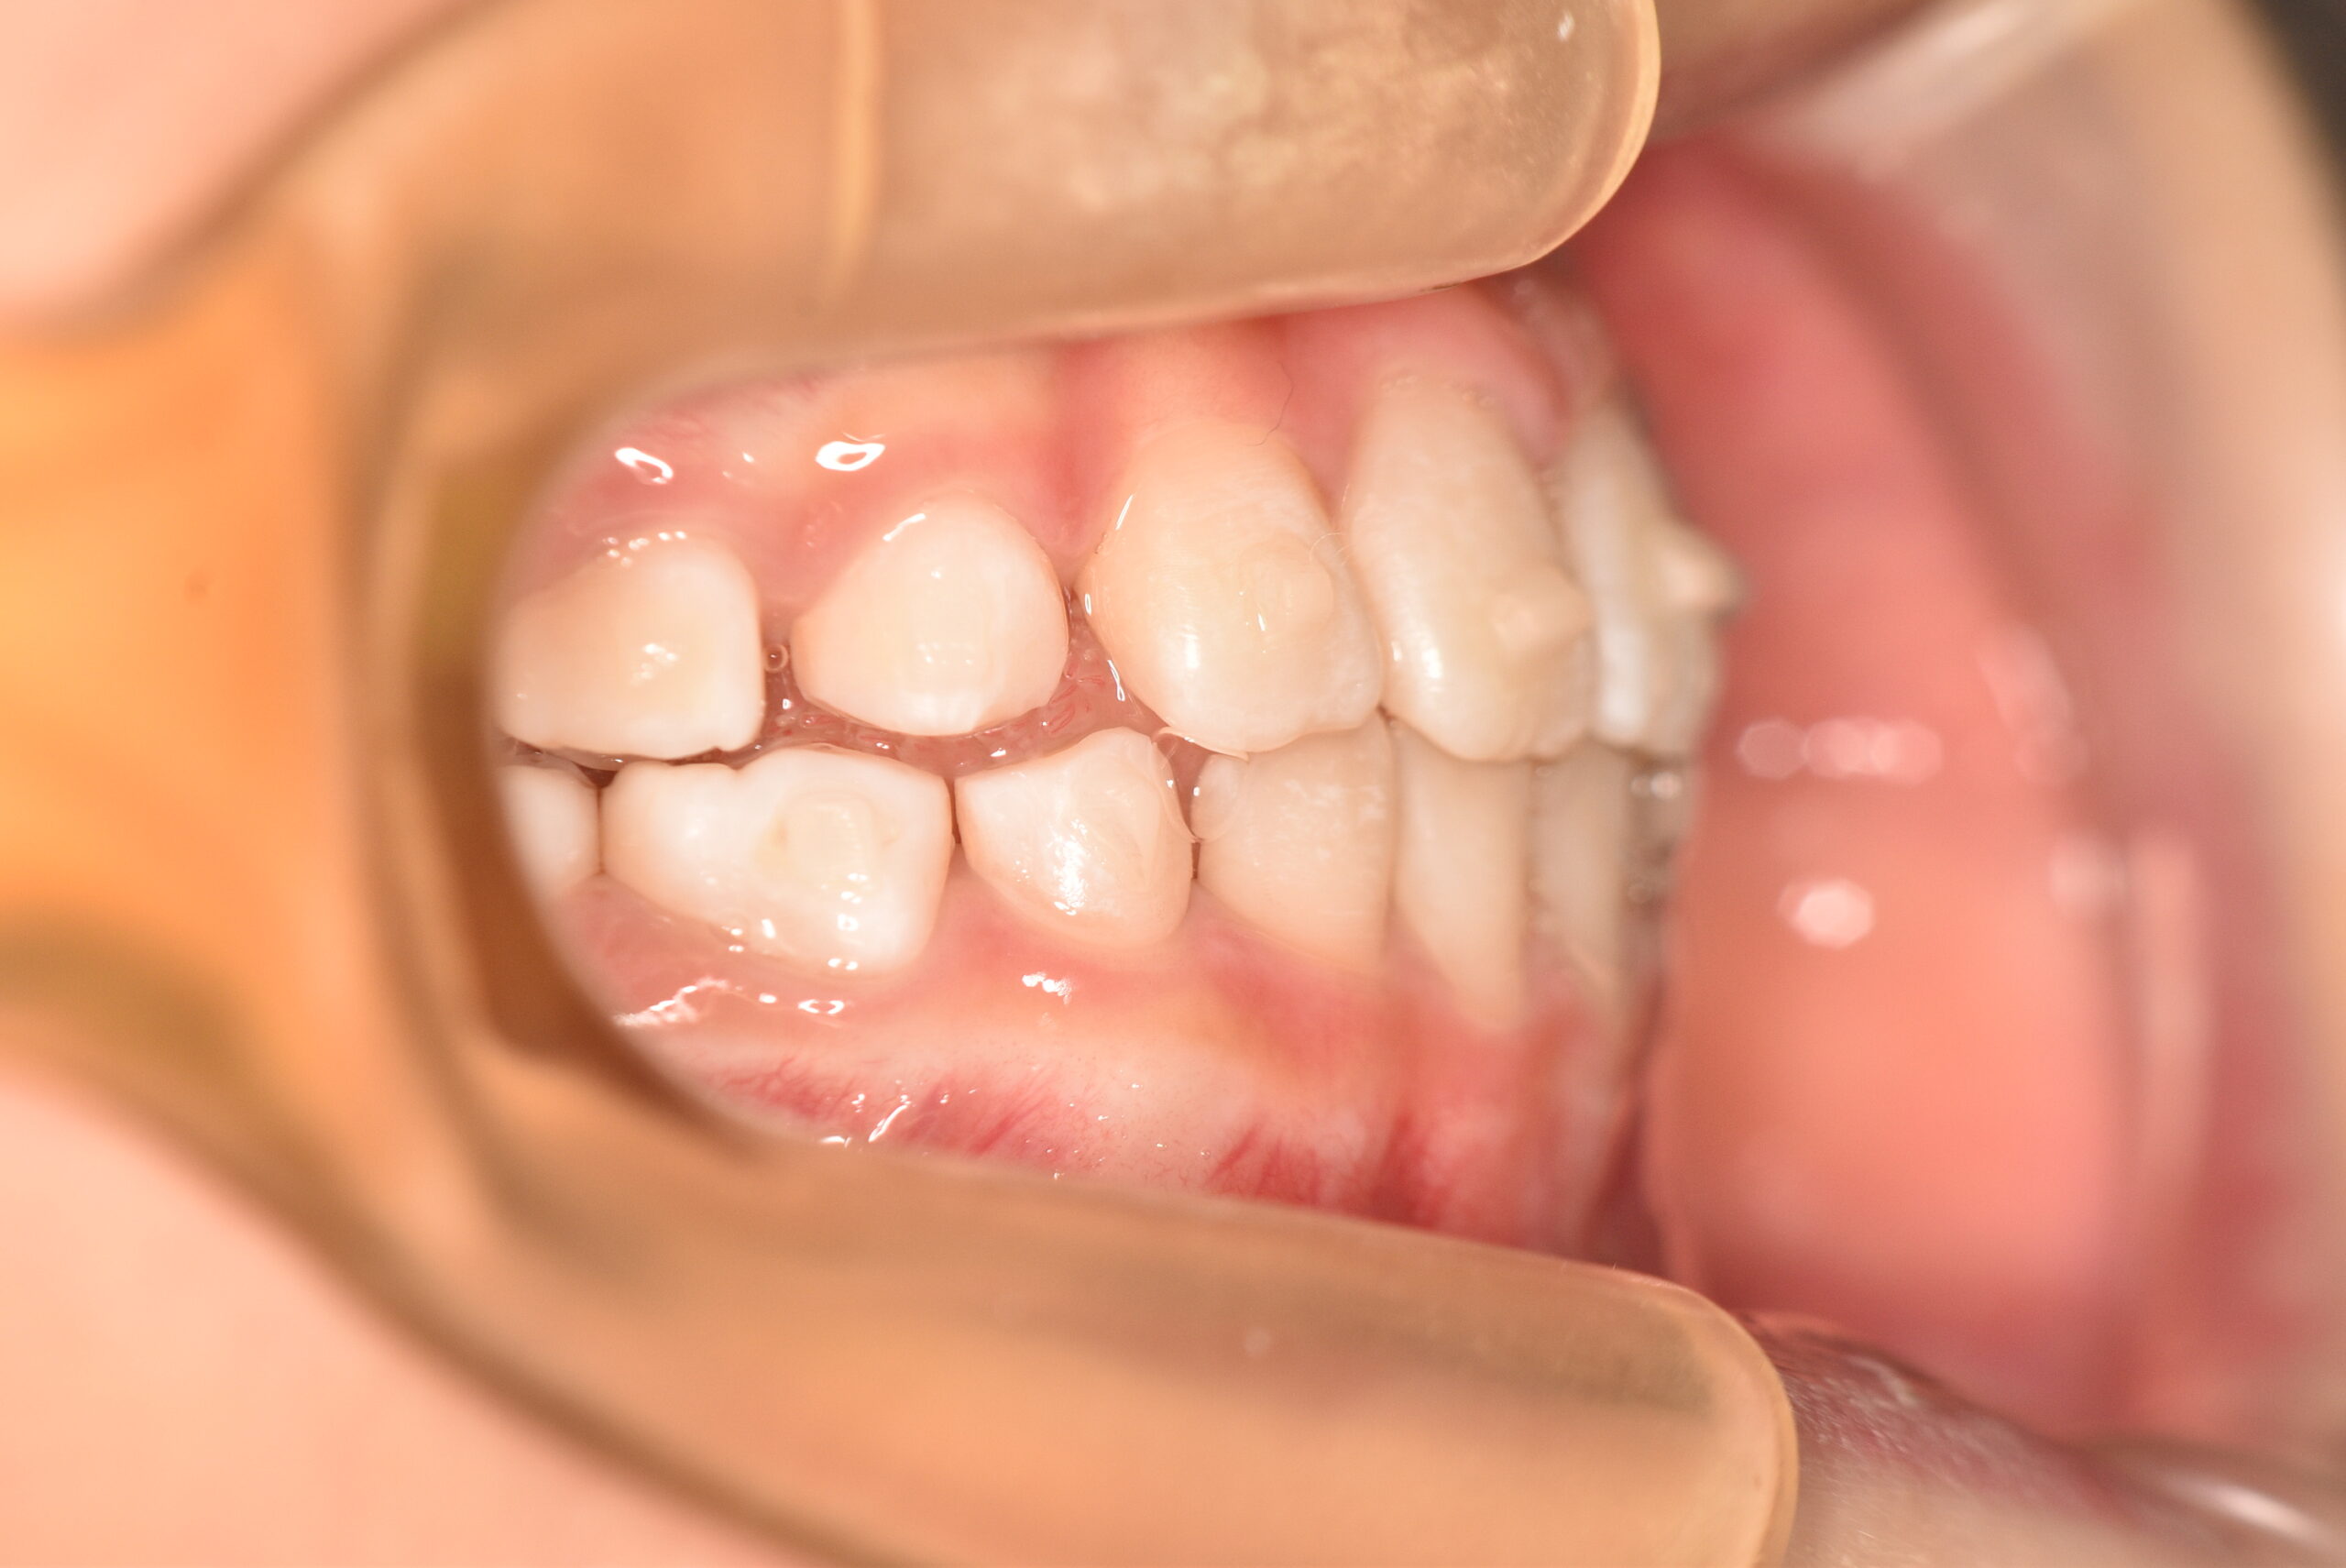

初診時

症例 症例 症例 症例

年齢

9歳 性 別 女性

治療内容の詳細 初診時9歳の女児で、歯のがたつきを気にされ来院されました。

検査の結果、前歯部叢生を伴うアングルⅠ級不正咬合と診断しました。

治療としてはマウスピース矯正(インビザラインファースト)で配列を行い、上下顎の側方拡大と萌出スペースを確保しました。

治療期間は、7ヶ月でした。

今後、側方歯生え変わりまで経過観察を行います。